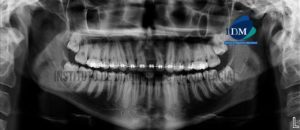

Paciente de sexo masculino de 54 años acude al Instituto de Diagnóstico Maxilofacial para evaluación del sector dentario posterior. A la evaluación de la radiografía